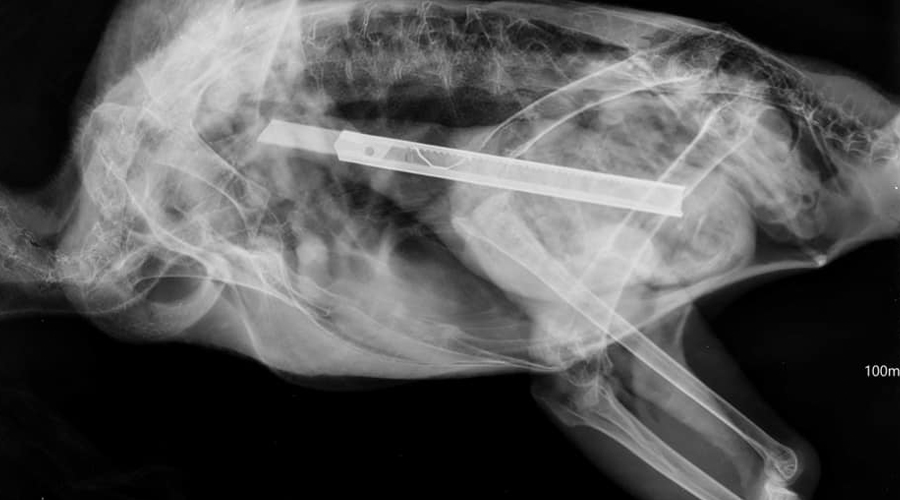

واقعة غريبة شهدتها جورجيا منذ أيام، حيث تم العثور على نسر بحاجة إلى عملية جراحية بسبب ابتلاعه مشرطاً.

ووفقاً لوكالة «سبوتنيك»الروسية، فإن فريقاً طبياً بيطرياً أجرى جراحة دقيقة لـ نسر، في جورجيا، بسبب ابتلاعه مشرطاً، وكان قد عثر سكان إحدى القرى المحلية على النسر الذي لم يستطيع الطيران، قبل أيام قليلة.

وأوضحت الوكالة، أن أحدهم توجه إلى حديقة حيوانات تبليسي، وبعد ذلك تم إخطار إدارة الإشراف البيئي أيضاً بحالة الطائر، وتم إحضار النسر إلى الحديقة من أجل إجراء جميع الدراسات اللازمة، وبعد ذلك تقرر تنفيذ العملية بواسطة نخبة من الأطباء البيطريين.